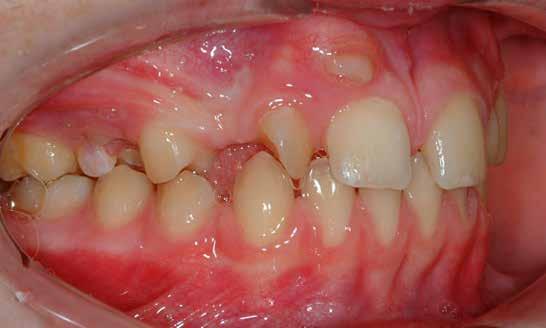

Lány páciensem I. fázisú kezelését 10 évesen kezdtük el bimaxilláris funkciós, kivehető készülékkel. Megfigyelhetőek a class 2-es eltérésnél tipikusan jellemző szűk felső és alsó fo-

gívek, valamint a nagy overjet, a mandibula disztál helyzete, továbbá a felső metszőfogak protrúziója, amelynek kialakulásához sokszor hozzájárul az ujjszopás is (1-3. képek)

A vegyes fogazati kezelési célok a fogívek tágítása és a mandibula meziális irányú növekedésének a biztosítása volt. Fontos, hogy az ilyen típusú készülékeket nem csak éjszaka, hanem napközben is – amennyit csak lehet – hordani kell a minél hatékonyabb működés érdekében. A 18 hónapos első fázisú kezelésnek köszönhetően az alap kezelési célok megvalósultak, sikerült a class 1-es okklúziót beállítani (4-7. képek).